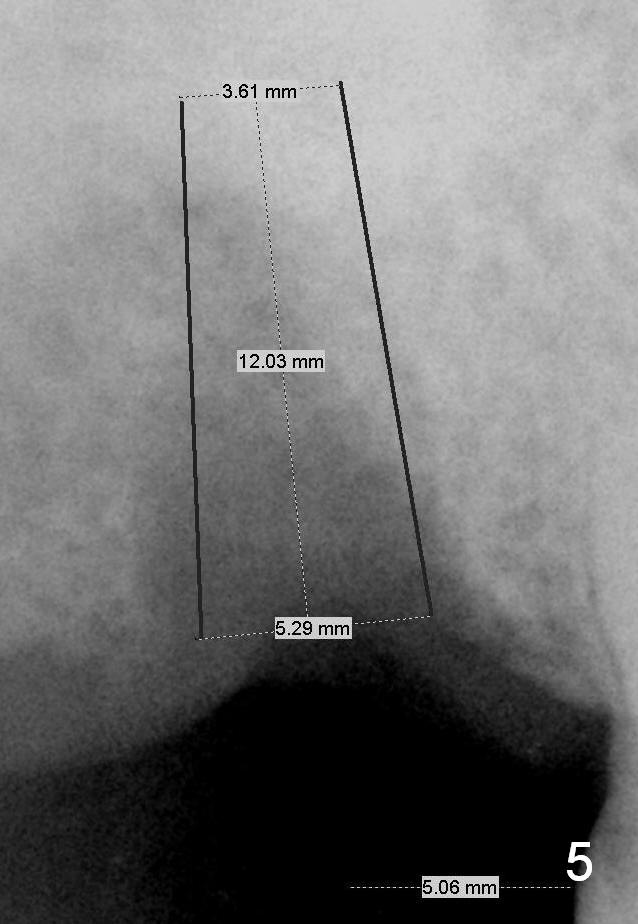

The smallest implant could be 5.3 mm (Fig.4,5). The short (10 mm, Fig.4) and long (12 mm, Fig.5) may be below and above the sinus floor, respectively.

If the stability of the 5x14 mm tap is not sufficient, insert 6x14 mm tap. Extra wide implants will be tried, either 5.9 or 6.4x10 mm (SM, Fig.6) or 6 or 6.5x12 mm (UF, Fig.7). An immediate provisional may be fabricated.